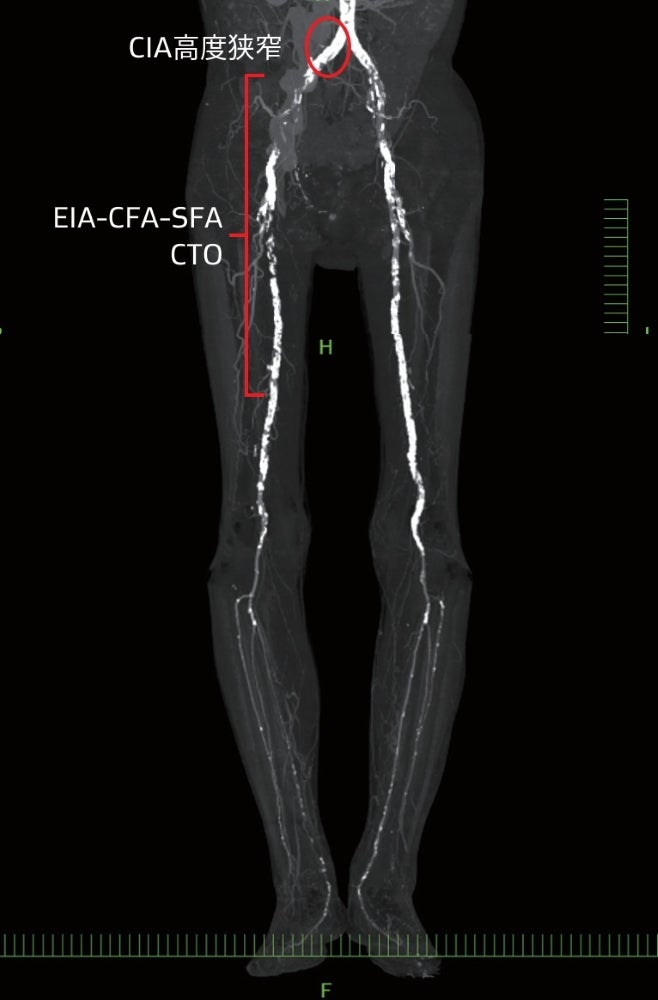

- 右総腸骨動脈(CIA)入口部の高度狭窄病変および右EIA-CFA-SFA全領域にわたるCTO病変

患肢はCIAの高度狭窄、EIA-CFA-SFAのCTOを合併し極めて高度な虚血状態であった。

術前のCTでは、いずれの病変も高度石灰化を伴っている(図2)。